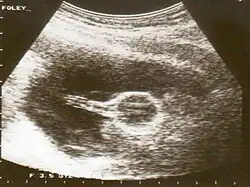

В рентгенологии катетер Фолея применяется при проведении гистеросальпингографии — диагностики с помощью рентгеновских лучей состояния фаллопиевых труб и внутренней полости матки. Двухходовой катетер Фолея диаметром 4,7—5 мм вводится внутриматочно, удерживающий баллон раздувается в объёме 2—3 мл, после чего через дренажный порт в матку вводится рентгеноконтрастный препарат. Рентгеновские снимки выполняются сразу после введения, затем через 10—15 минут, затем, если в этом есть надобность, через 24 часа[4].

Использование катетера Фолея при гистеросальпингографии имеет ряд преимуществ по сравнению с традиционными методами: в частности, обеспечивается полная герметизация матки, а проведение процедуры является менее болезненным[4].